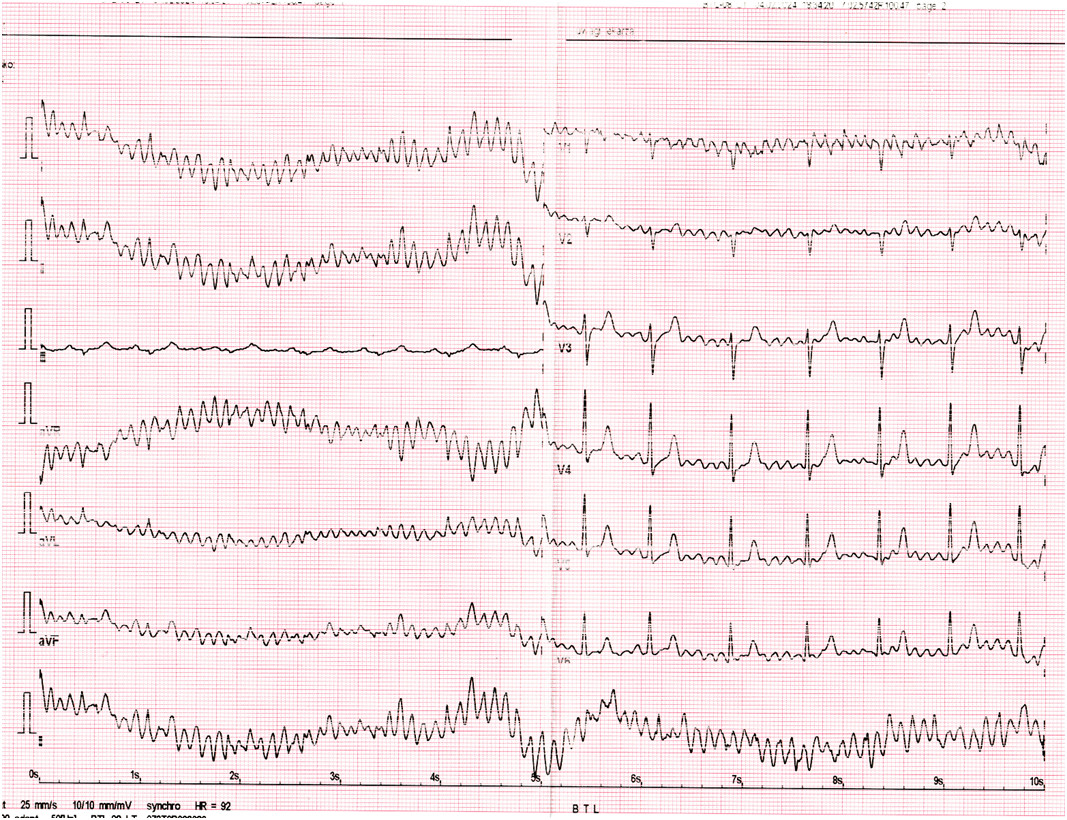

86-letni mężczyzna 3-krotnie zemdlał w ciągu ostatniego tygodnia. Omdlenia nie były poprzedzone żadnymi objawami. Przy ostatnim omdleniu pacjent uderzył się w głowę, był splątany przez 15 minut, ale obecnie nie ma żadnych deficytów neurologicznych. W TK głowy bez istotnych patologii, ranę pacjenta na głowie zaopatrzono. W trakcie monitorowania EKG na SOR zapis jak poniżej. Jakiego typu omdlenie najprawdopodobniej miał pacjent i jaka powinna być decyzja dotycząca hospitalizacji?